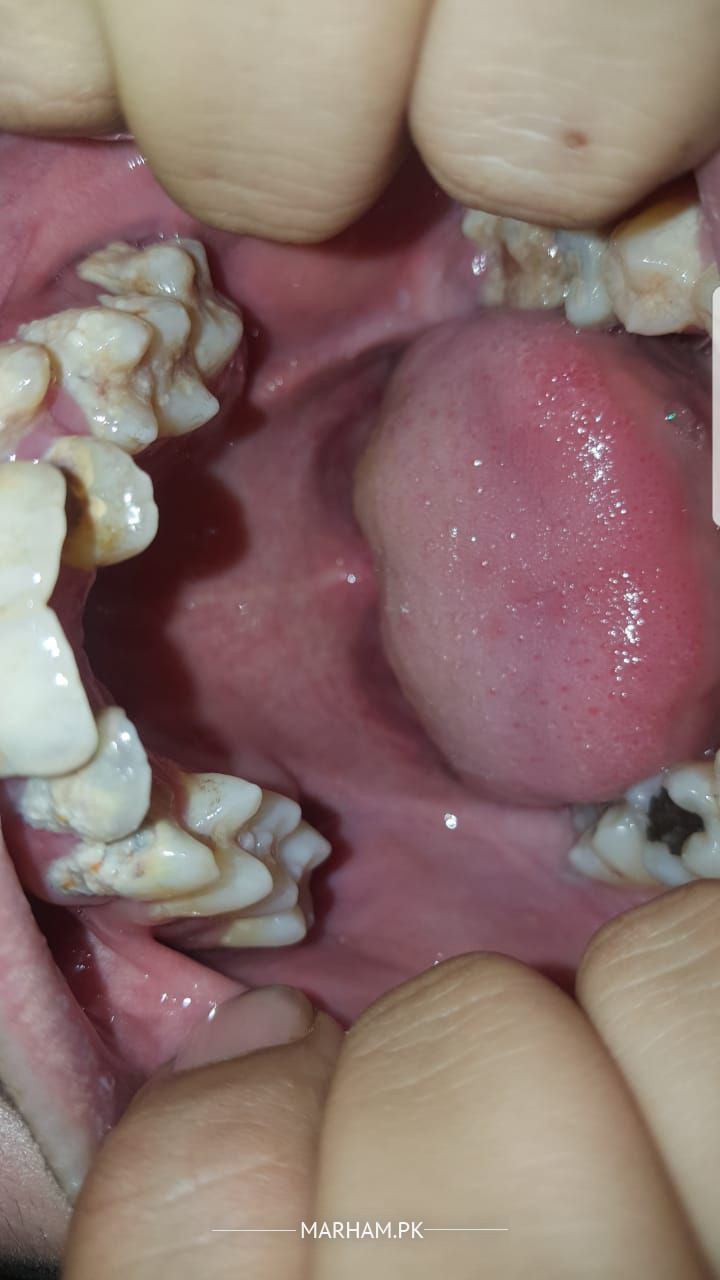

I have had teeth problems since i was a child now iam 20 and starting to lose hope if my teeth are fixable or not i have alot of cavities in my teeth and they are misaligned and are sensitive to hot and cold my lower left teeth is pretty much fully decayed so i cant eat and is very sensitive to anything please guide me for my problems thanks

There is Calculus and Carries need only SPT and Light cure Composite Filling

You need many fillings and have crooked teeth as seen in the pics. You may visit any good dentist to make a proper plan for fixing your dental problems.

you need to visit Clinic for proper treatment. u need treatment of malignant plus multiple cavities and scaling.

u feel hot n cold due to these cavities u require immediate fillings n might b root canals which could b confirmed after clinical examination n x-ray. kindly visit nearby dentist for proper treatment plan of ur teeth

your problem Is multidisciplinary ,

1. poor oral hygiene,

2. cavities needing urgent restorations alongwith

3. Orthodontic Treatment for teeth alignment and prevention of future problem.